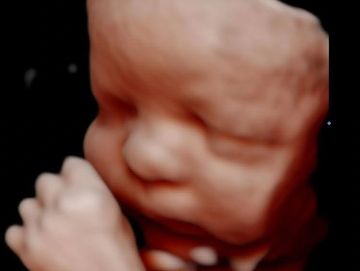

Memories that last a lifetime.